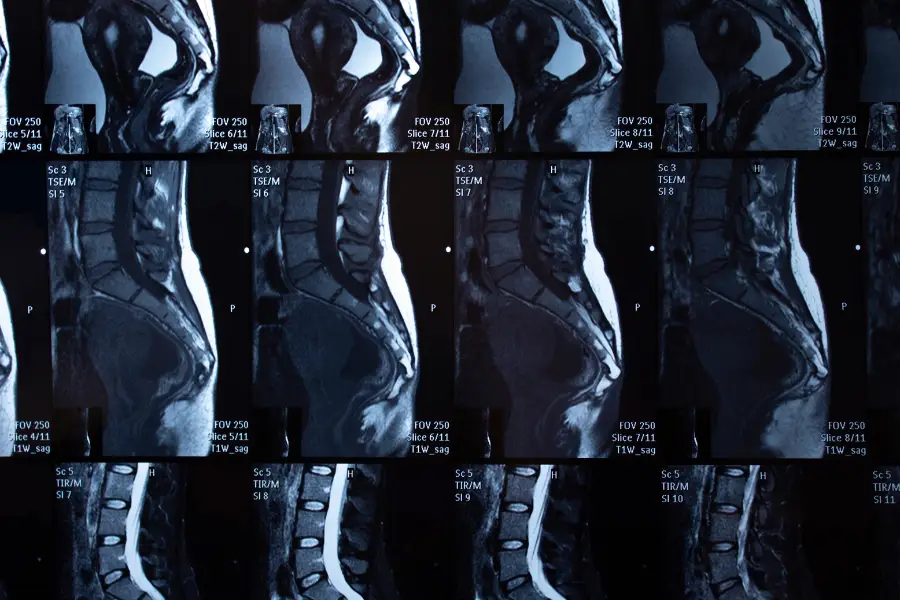

MRI and Back Pain: What Imaging Really Shows — and What It Doesn’t

MRI has changed spine diagnostics — but it has also created new misconceptions

Magnetic resonance imaging (MRI) is one of the most powerful diagnostic tools in modern medicine. In patients with back pain, it is often perceived as the definitive answer — a test that can explain every symptom and dictate the correct treatment.

In reality, MRI is a tool, not a diagnosis.

Understanding what MRI can reveal — and what it cannot — is essential for making safe and informed clinical decisions.

What MRI is actually designed to show

MRI provides detailed visualization of soft tissues, including:

- intervertebral discs;

- spinal cord and nerve roots;

- ligaments and facet joints;

- inflammatory or structural changes.

It is particularly valuable for identifying:

- disc herniation or extrusion;

- spinal canal stenosis;

- tumors, infections, or inflammatory processes;

- nerve compression correlating with neurological symptoms.

When interpreted correctly and in the proper clinical context, MRI is indispensable.